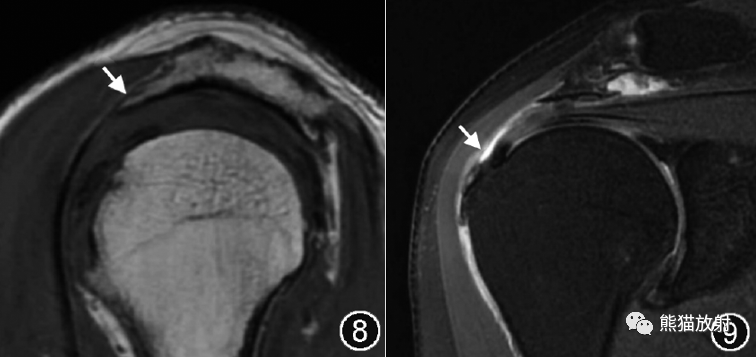

图8,9 喙肩韧带附着处骨刺伴肩峰下撞击综合征的MR图像。肩关节MR平扫斜矢状面T1WI(图8)示喙肩韧带肩峰附着处骨刺形成(↑),肩峰下间隙狭窄,斜冠状面脂肪抑制T2WI(图9)示冈上肌腱信号增高、滑囊面纤维不连续(↑),肩峰下-三角肌下滑囊积液、滑膜增生